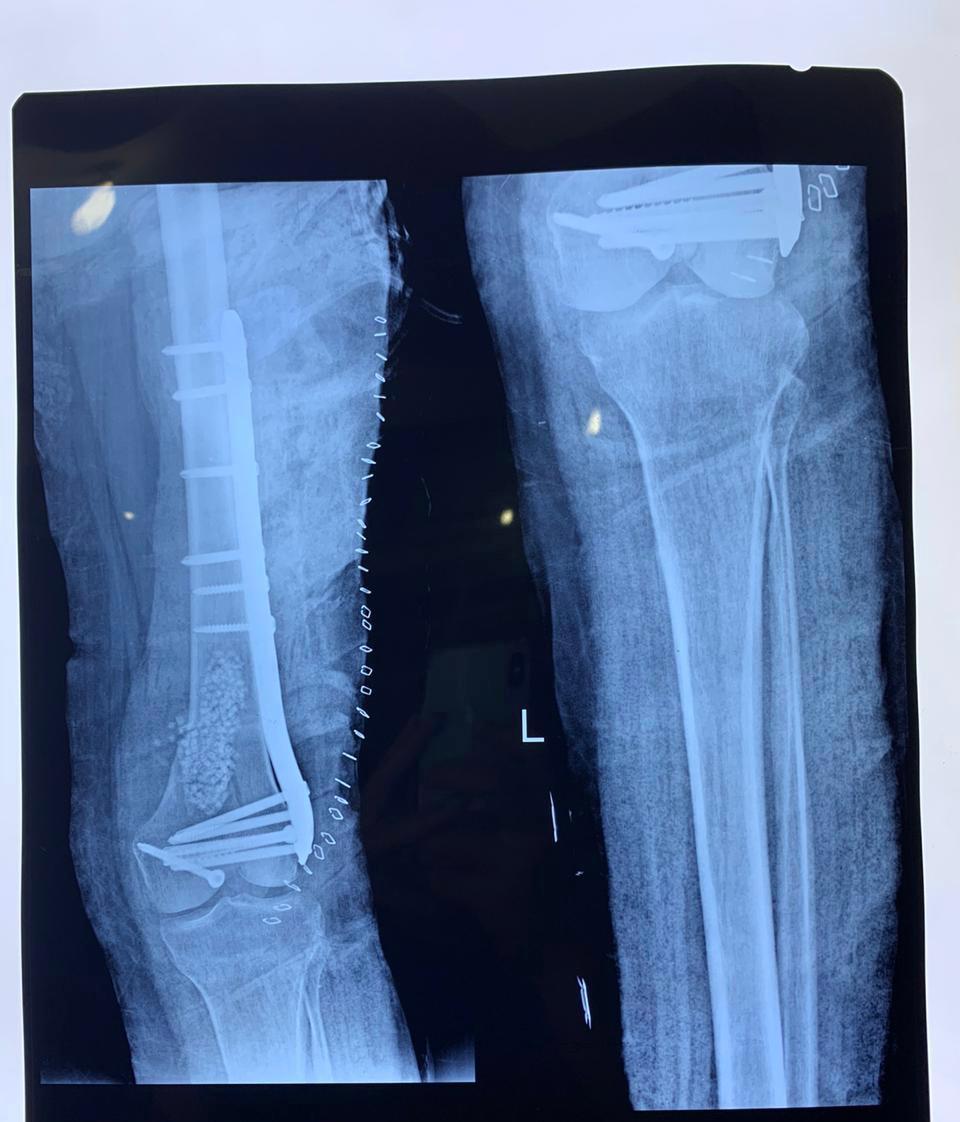

Trauma surgeries focus on the management of complex injuries resulting from accidents, falls, or high-impact trauma. Prompt surgical intervention is provided to stabilize injuries, promote proper healing, and restore function while minimizing long-term complications.

We provide surgical management for fractures involving the upper and lower limbs, including arms, forearms, thighs, legs, and ankles. Treatment aims to achieve proper bone alignment, stable fixation, and optimal functional recovery through modern orthopedic techniques.